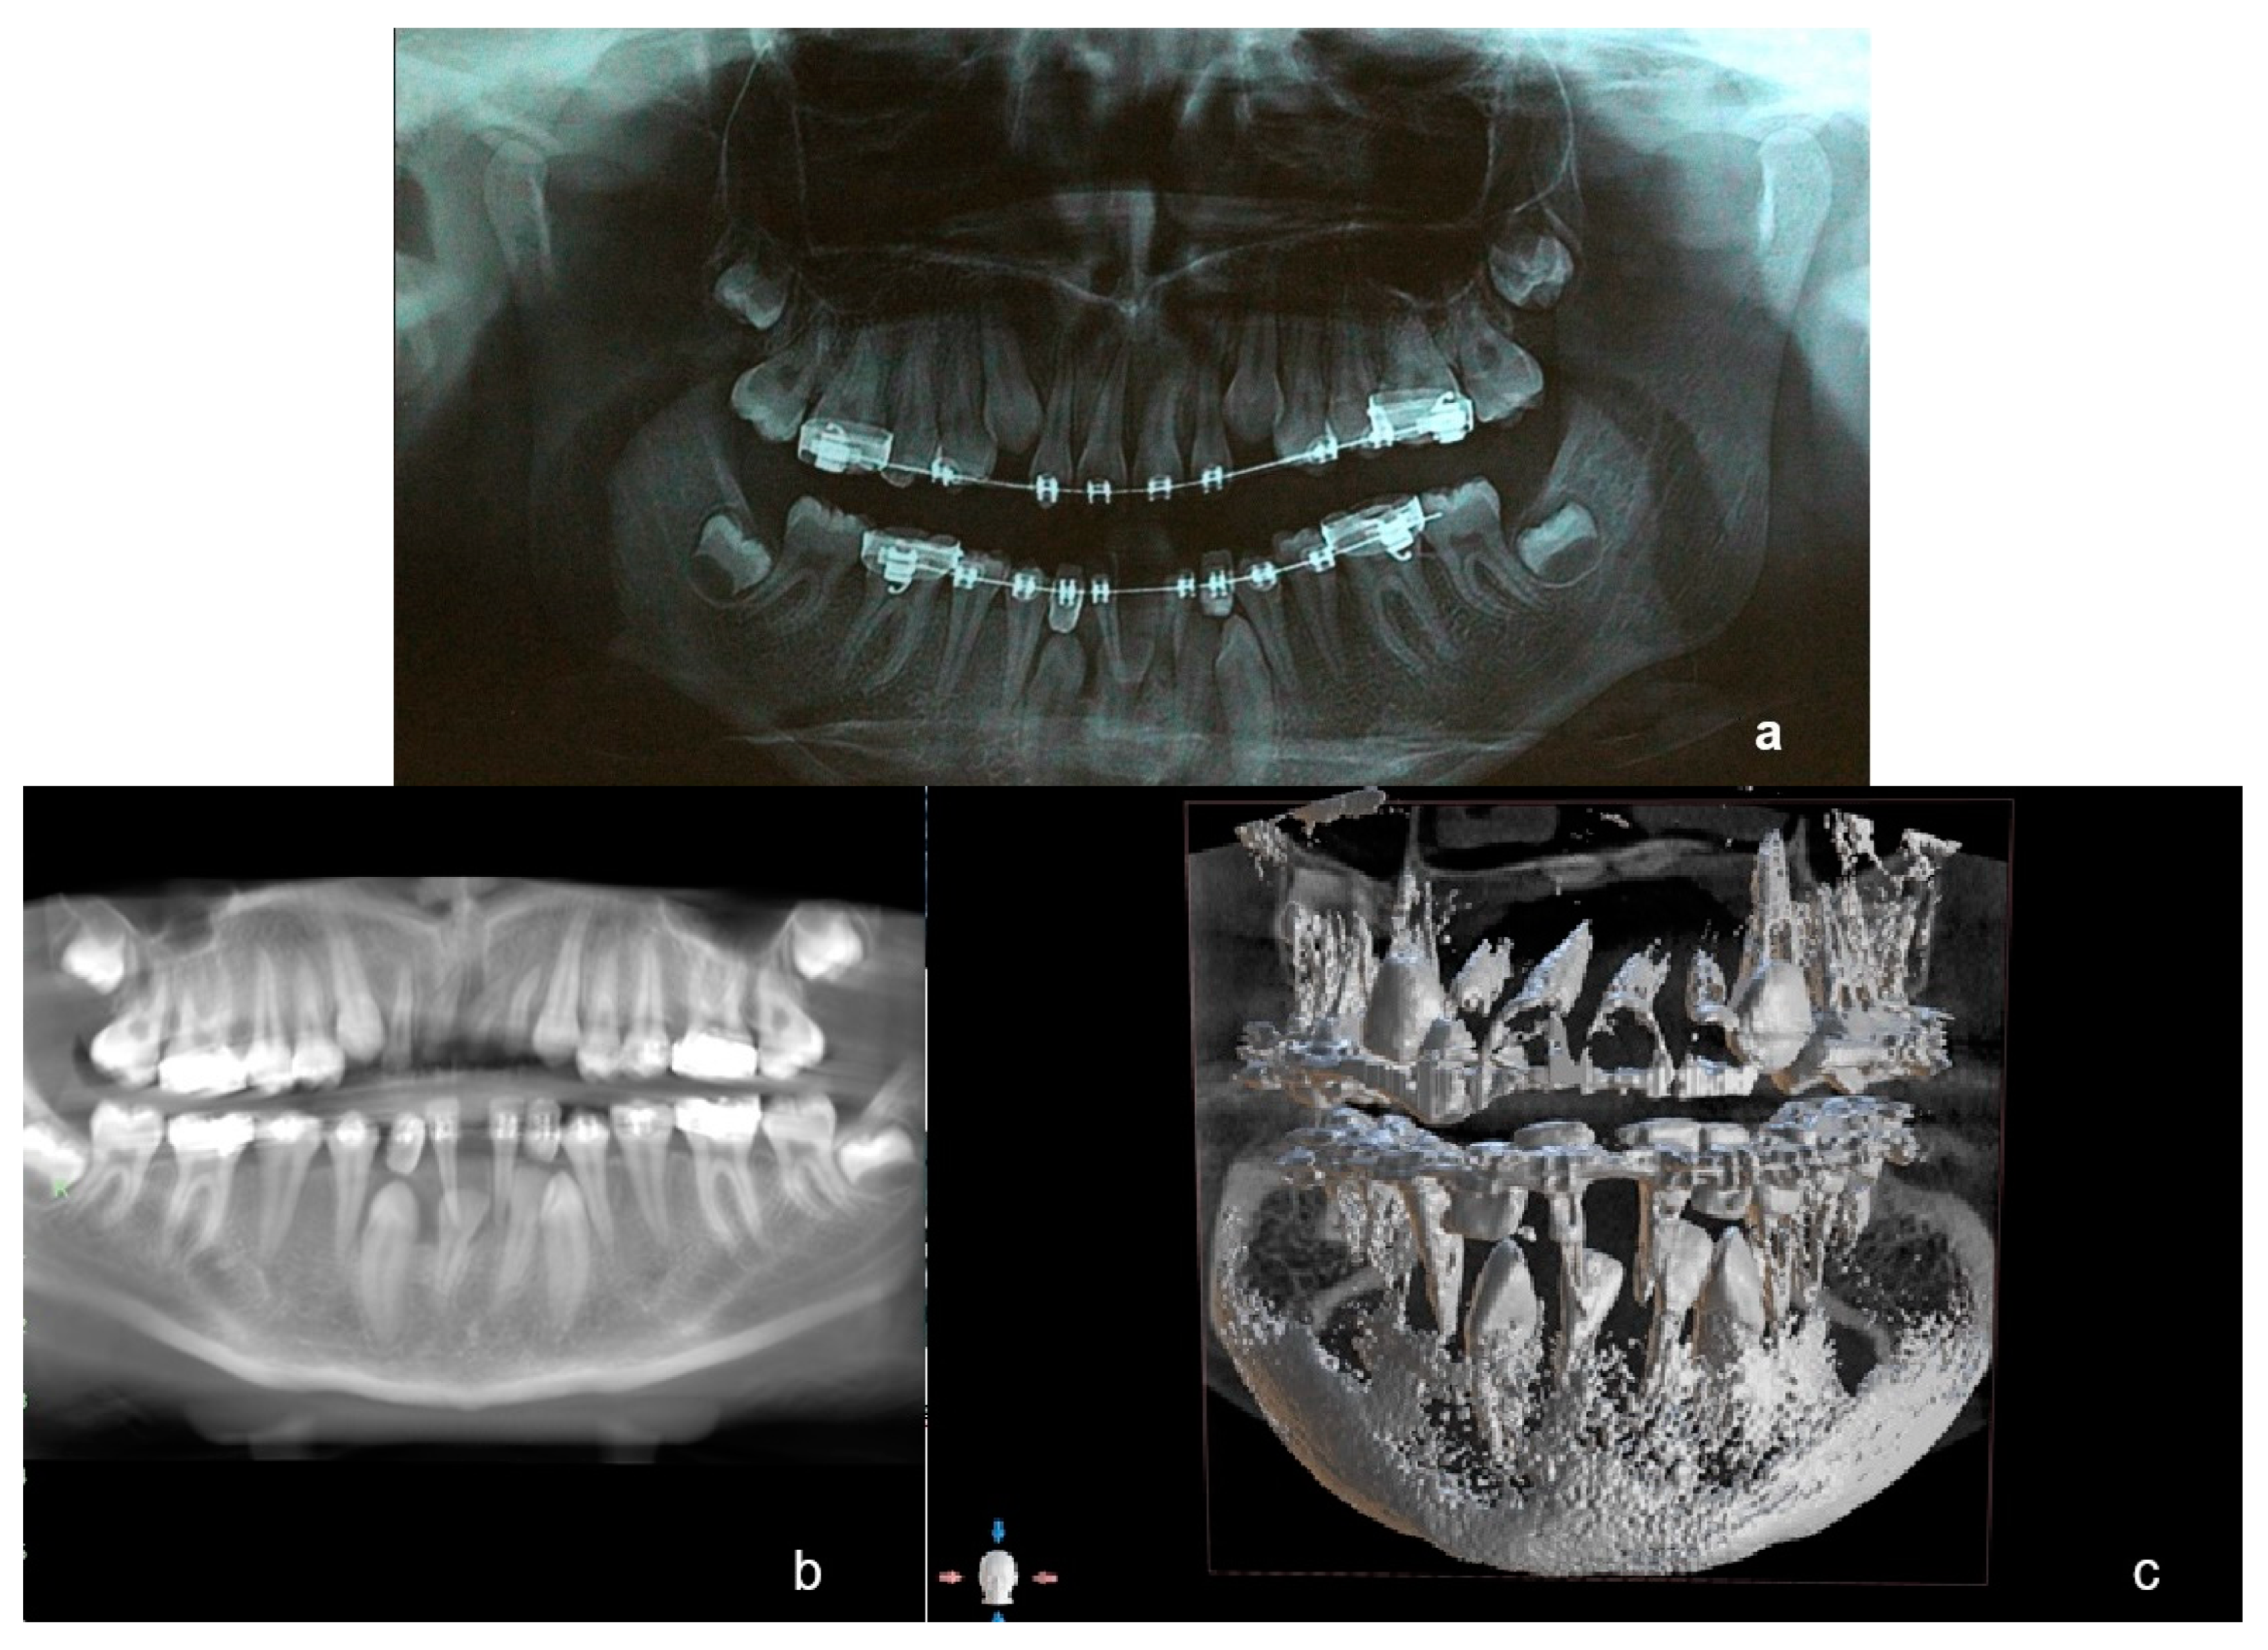

Several months later a new panoramic radiograph (Figure 6a) and a subsequent (3 months later) cone-beam computed tomography (CBCT) (Figure 6b,c) were performed. The shape and configuration of the roots of 11 and 21 was noted on those illustrations as they presented significant deformation, while 42 had a decreased size of the root. As the roots of lower deciduous central incisors were intact, it was decided not to extract them for the moment, as they could be utilized to enhance anchorage for the orthodontic traction of impacted incisors and canines. It was also decided to open the space between them in order to obtain space in the arch as there might be a spontaneous eruption of 42. Additionally, a high pull headgear was fitted in order to achieve an upwards rotation of the mandible and deal with the skeletal Class II relationship.

Figure 6. A second progress panoramic X-ray (a) and a subsequent (3 months later) CBCT (b) panoramic view of CBCT and (c) 3D view of CBCT), where deformation of roots of 11, 21, 22, and a decreased size of the root of 42 are noted.